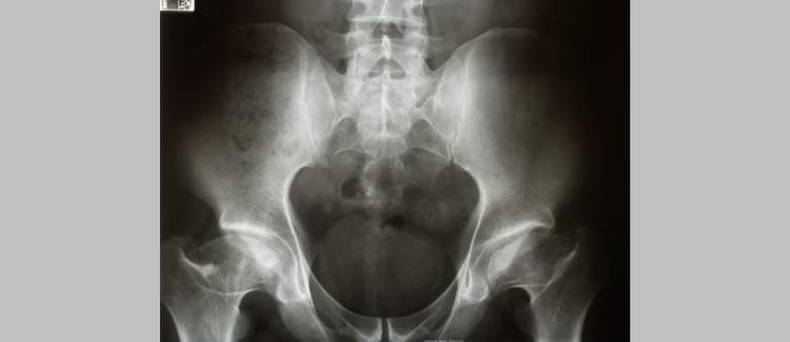

Door middel van radiografie wordt de diagnose gesteld.

Vaak zal de hond een roesje krijgen voor dit onderzoek. Hij wordt dan op de rug gelegd en de poten worden loodrecht naar achter getrokken. Dit is pijnlijk. Naar aanleiding van de ernst die waargenomen wordt zal een beoordeling worden gegeven van A tot D aan alle twee de heupgewrichten. Hierbij is  A het beste resultaat is. Rashonden die voor de fok worden gebruikt moeten beoordeeld worden door de keuringscommissie. Ze mogen alleen gebruikt worden voor de fok als ze voldoen aan de vereisten.Bron foto: Joel Mills